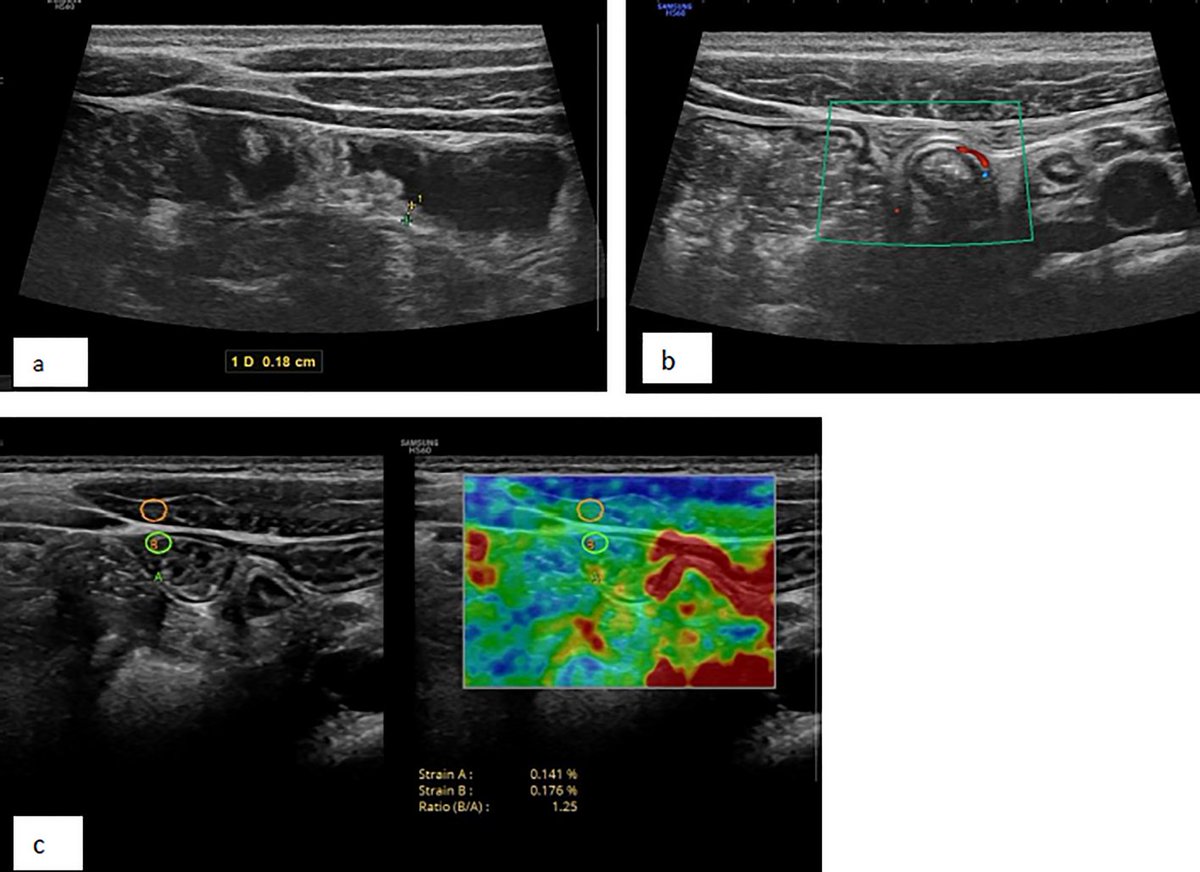

Ultrasound-guided preoperative skin-marking for deep inferior epigastric perforator flap surgery dlvr.it/TDdS6b